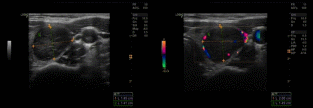

超声所见:甲状腺双叶弥漫性改变,回声不均,内见许多散在低回声区,左叶中部见一个实性低回声区,大小约28×14mm,形态规则,边界清,内部回声不均匀,CDFI:其周边及内部见较丰富血流信号,TI-RADS-3级。